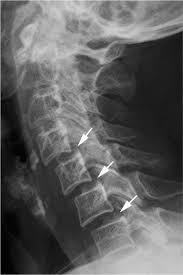

Q

1. Atlantoaxial Subluxation:

* Dx/Most common findings on XR?

A

• 1st stage of spine involvement in RA

- 50-80% of RA patients

- Pannus formation at synovial joints b/t dens and ring of C1 resulting in destruction of transverse ligament, dens, or both

- Leads to instability b/t C1 and C2

- Dx: anterior subluxation of C1 on C2 most common finding.

Xrays to determine AADI and PADI:

- 3.5 mm on flex/ex

- PADI <14 mm more sensitive than AADI measurement for spinal cord compression in patients w/ RA. More sensitive for identifying patients at risk of neuro injury.

Surgery:

- - C1 lateral mass-C2 pedicle/pars fixation (Harms construct) using polyaxial screws

□ Lower rates of vert and C2 n. injury

□ Strongest biomechanical construct

Does not require C1-2 reduction

How well did you know this?

Xrays determine instability, what radiology parameters do I need to look at? Which one is more sensitive?

Xrays determine mechanical instability: c1-c2 relationship.

* AADI >9-10 mm= surgery due to risk of neurologic injury

* PADI <14 mm= surgery due to risk of neurologic injury

* 3.5 mm on flexion/ext views, though radiographic instability is common in RA and not necessarily indication for surgery.

PADI <14 mm more sensitive than AADI measurement for spinal cord compression in patients w/ RA. More sensitive for identifying patients at risk of neuro injury.

AAOS: patients with rheumatoid arthritis and neurologic deterioration in C1-2 instability are more likely to achieve some improvement if the posterior atlanto-dens interval is greater than 10 mm on preoperative studies. All the patients in their series who had neurologic deterioration and a preoperative posterior atlanto-dens interval of greater than 14 mm achieved complete motor recovery.